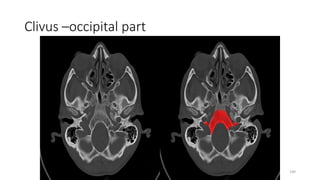

Clivus –occipital part

Basiocciput (posterior clivus)